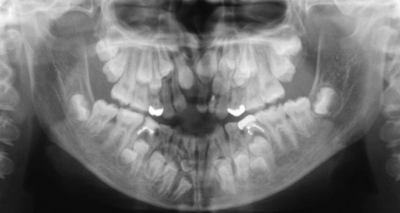

13 歳の女子。前歯が嚙まないことを主訴として来院した。低身長である。初診時の顔面写真、口腔内写真及びエックス線画像を別に示す。

認められるのはどれか。2つ選べ。

a. 下顎角の開大

b. 上顎骨の過成長

c. 前歯の萌出遅延

d. 第一大臼歯の挺出

e. デンタルコンペンセーション

適切な治療方針はどれか。3つ選べ。

a. 過剰歯の抜去

b. 残存乳歯の抜去

c. 埋伏歯の開窓牽引

d. 下顎切歯の唇側傾斜

e. 上顎大臼歯の遠心移動